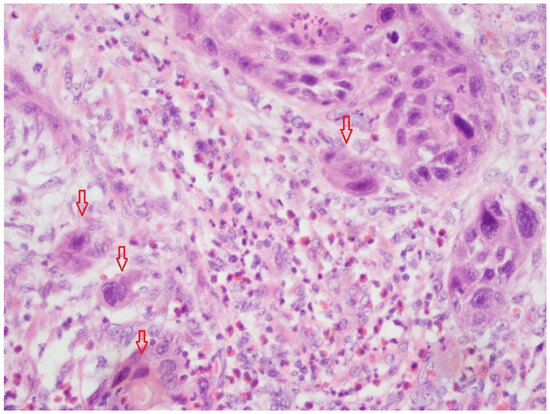

Extracapsular Lymph Node Involvement in Ovarian Carcinoma

by Sabine Heublein, Heiko Schulz, Frederik Marmé, Martin Angele, Bastian Czogalla, Alexander Burges, Sven Mahner, Doris Mayr, Udo Jeschke and Elisa Schmoeckel

Cancers 2019, 11(7), 924; https://doi.org/10.3390/cancers11070924 - 1 Jul 2019

Ovarian cancer (OC) spread to retro-peritoneal lymph nodes is detected in about one out of two patients at primary diagnosis. Whether the histologic pattern of lymph node involvement i.e., intra-(ICG) or extracapsular (ECG) cancer growth may affect patients’ prognosis remains unknown. The aim [...] Read more.

Ovarian cancer (OC) spread to retro-peritoneal lymph nodes is detected in about one out of two patients at primary diagnosis. Whether the histologic pattern of lymph node involvement i.e., intra-(ICG) or extracapsular (ECG) cancer growth may affect patients’ prognosis remains unknown. The aim of the current study was to analyze the prevalence of ECG and ICG in lymph node positive ovarian cancer. We further investigated whether ECG may be related to patients’ prognosis and whether biomarkers expressed in the primary tumor may predict the pattern of lymph node involvement. Lymph node samples stemming from 143 OC patients were examined for presence of ECG. Capsular extravasation was tested for statistical association with clinico-pathological variables. We further tested 27 biomarkers that had been determined in primary tumor tissue for their potential to predict ECG in metastatic lymph nodes. ECG was detected in 35 (24.5%) of 143 lymph node positive patients. High grade (p = 0.043), histologic subtype (p = 0.006) and high lymph node ratio (LNR) (p < 0.001) were positively correlated with presence of ECG. Both ECG (p = 0.024) and high LNR (p = 0.008) were predictive for shortened overall survival. A four-protein signature determined from the primary tumor tissue was associated with presence of concomitant extracapsular spread in lymph nodes of the respective patient. This work found extracapsular spread of lymph node metastasis to be a common feature of lymph node positive ovarian cancer. Since ECG was positively associated with grade, LNR and shortened overall survival, we hypothesize that the presence of ECG may be interpreted as an indicator of tumor aggressiveness. Full article